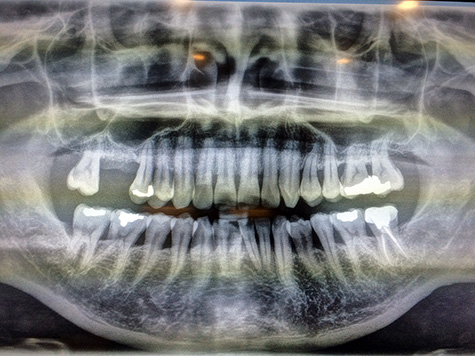

the chinese head nurse called me inside. the first thing we did was to take a panoramic x-ray of my teeth, to check on the status of the bone graft i had done back at the end of december. the bone had bonded perfectly, no problems from the x-ray.

with that i was done, just had to take another x-ray to make sure everything was okay. i sort of stumbled to the panoramic x-ray machine, almost dropping my glasses, and banging my forehead against one of the adjustable head brace prongs.

back in the operating room, we looked at the x-ray. now instead of an empty gap was the silhouette of the dental implant. i now officially join the ranks of metahumans in being part flesh and part metal! when i asked the doctor if it was a titanium implant, he said no, but something even better, even though he didn't say what it was. the operation was a complete success, no complications whatsoever. my sinus cavity was intact, just pushed up a little bit to make room for the additional bone graft. my right nostril felt stuffed up, the doctor said this was normal after a sinus lift (it cleared up soon after i left). he said that my jawbone was the optimal hardness level (scoring 35 on this fancy bone hardness meter), so the implant is extremely stable.